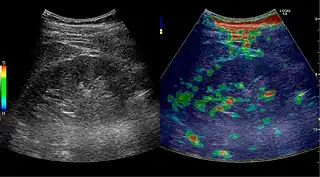

Solid malignant tumors in the kidney do not exhibit specific enhancement patterns like some liver lesions, and no valid enhancement criteria between benign and malignant renal lesions have been proposed. However, CEUS is used in some patients after ablation of renal cell carcinoma to evaluate contrast uptake in the treated area (Figure 30).

Image fusion of ultrasound with a previously recorded dataset of CT or other modalities is rarely used in renal US. Reports on image fusion using CEUS or US combined with CT or MRI in the examination of renal lesions and in difficult US-guided renal interventions have been published (Figure 31). However, no recommendations have been published so far.[1]

Elastography is a US method to visualize the elasticity of tissue. Preliminary reports on US elastography used on transplanted kidneys to evaluate cortical fibrosis have been published showing promising results (Figure 32).[1]

Figure 31. Unspecific cortical lesion on CT is confirmed cystic and benign with contrast-enhanced ultrasound (CEUS) using image fusion.[1]

Figure 32. Strain elastography of a normal kidney. Red depicts soft areas, and blue depicts hard areas relative to the entire elastography image. Note that the medulla is softer than the cortex. A color bar is shown to the left of the image, where "S" and "H" denote soft and hard tissue, respectively.[1]